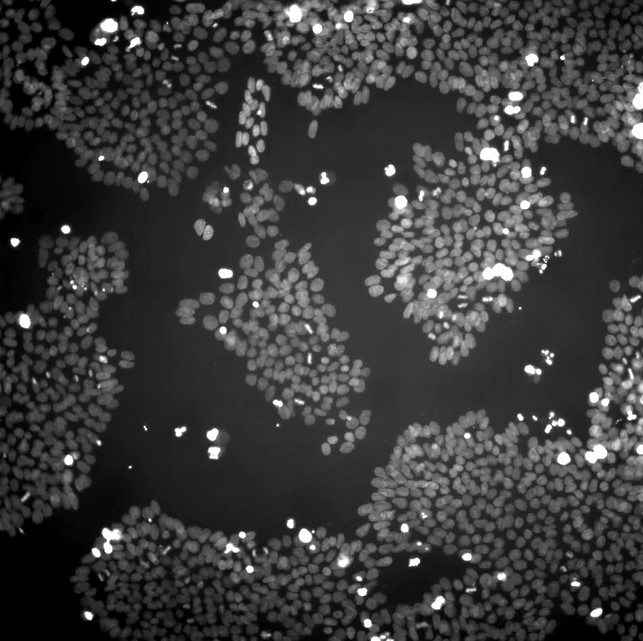

CellVoyant’s new product, a platform called FateView, aims to significantly reduce the waste in this process by using AI models it has trained to classify cells by their current qualities and, critically, predict which cells will possess the right qualities in the future, simply by analyzing microscope-based imagery of the cells that use regular, white light. Currently the platform can do this for 10 different cell types—including stem cells, T-cells, cardiac cells, and blood cells—and the company is planning on training its models to work with more in the future.

The company’s platform can, according to CellVoyant, instantly identify which cells are currently exhibiting certain biomarkers, predict how well individual cells will express certain genes in the future, and forecast how well stem cells will differentiate into specific cell types—all from white light microscope images, without having to perform chemical tests that are time-consuming and can destroy cells in the process.

Carazo Salas, who is also a professor of cellular and molecular medicine at the University of Bristol, in England, said CellVoyant was able to train AI models to characterize cells and predict their behavior because it had access to a large database of microscope images of the same cells taken over time, as well as the results of traditional chemical assays on cells taken at different stages of development. This time-series data allows the models to learn how the shape and visual characteristics of a cell at any point relate to its current function, as well as how it relates to its future appearance and function. The company trains a specific model for each cell type it works on—for instance, a separate model for cardiac cells and one for metabolic cells—although it is possible that in the future a single foundation model might be able to learn how to make predictions about any cell type, Carazo Salas said.